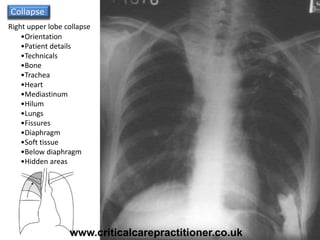

Collapse of the

lung is pulling the

trachea towards it

due to volume loss

Horizontal fissure

pulled upwards

Right upper lobe collapse

Collapse

•Orientation

•Patient details

•Technicals

•Bone

•Trachea

•Heart

•Mediastinum

•Hilum

•Lungs

•Fissures

•Diaphragm

•Soft tissue

•Below diaphragm

•Hidden areas